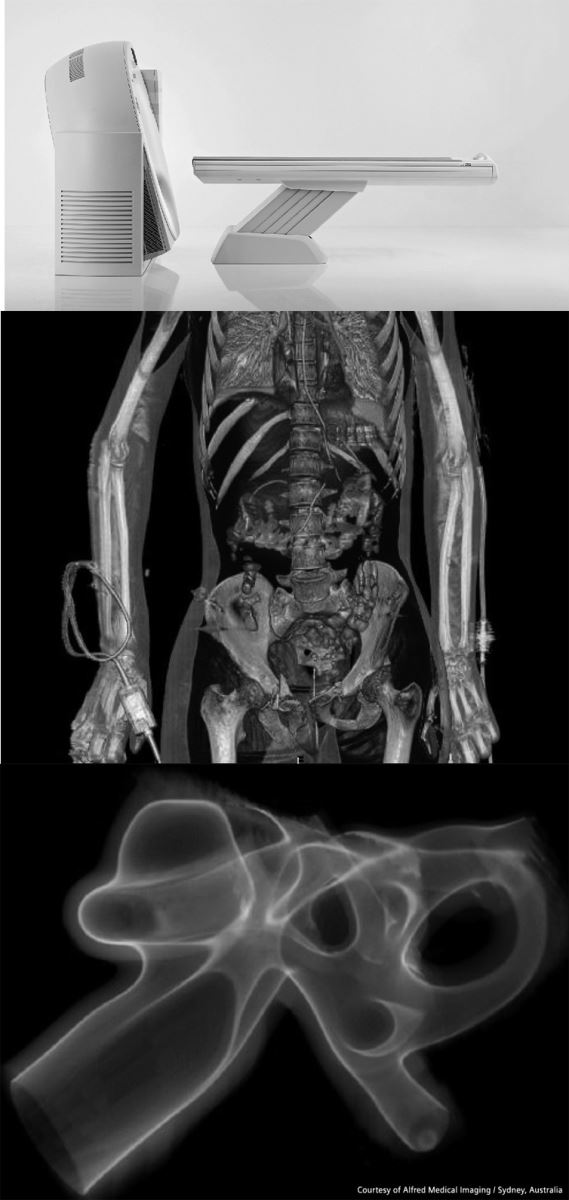

德国西门子SomAToM Emotion 16层螺旋CT是目前国际先进的环保型第二代新概念螺旋CT,该设备在临床应用方面具有以下优势:

2、动脉造影技术(CTA):对造影剂团注技术,造影剂自动追踪技术,快速扫描和立体重建技术等多项先进技术的综合应用,可清晰显示:如大动脉、脑动脉、肾动脉、肺动脉和下肢动脉等人体各重要血管。对大动脉狭窄,主动脉夹层,肺栓塞,脑动脉瘤等多种疾病能清晰显示和明确诊断,相比心血管造影检查具有无创、和费用低的优点。

3、多平面成像(MPR)技术:能完成对人体任一检查部位的横断、冠状、矢状和曲面成像,且任一断面图像质量不变,保证多角度准确显示病灶或正常解剖结构的特点。

4、立体容积重建(VR)技术:本系统利用多种重建技术,可以做到任一解剖位置的立体成像,突出显示重点部位,解决了复杂部位结构的重叠问题,为制定治疗方案提供准确的依据。